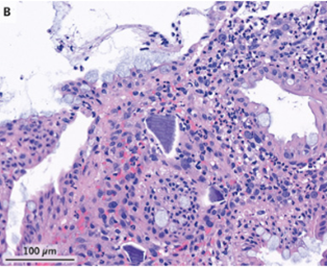

結腸粘膜生検が施行され、壊死炎症を背景に上皮損傷と好塩基性ポリスチレンスルホン酸Ca結晶が認められた。